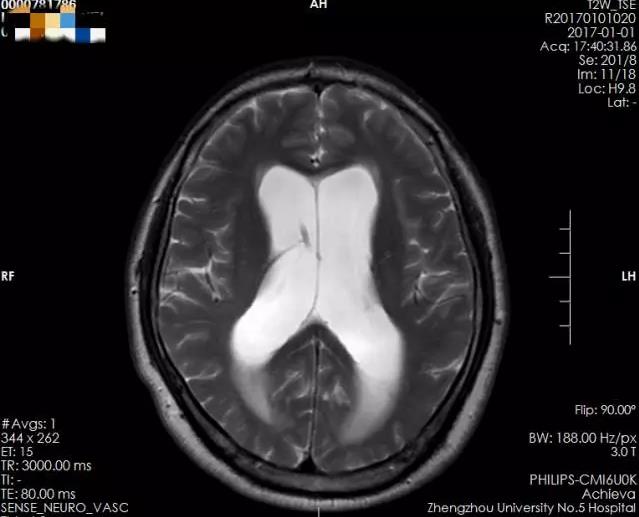

术前侧脑室、三脑室均增大,并有室旁水肿,测量三脑室大小约1.49cm

术后侧脑室及三脑室较前明显缩小,室旁水肿基本消失,测量三脑室大小约1.10cm